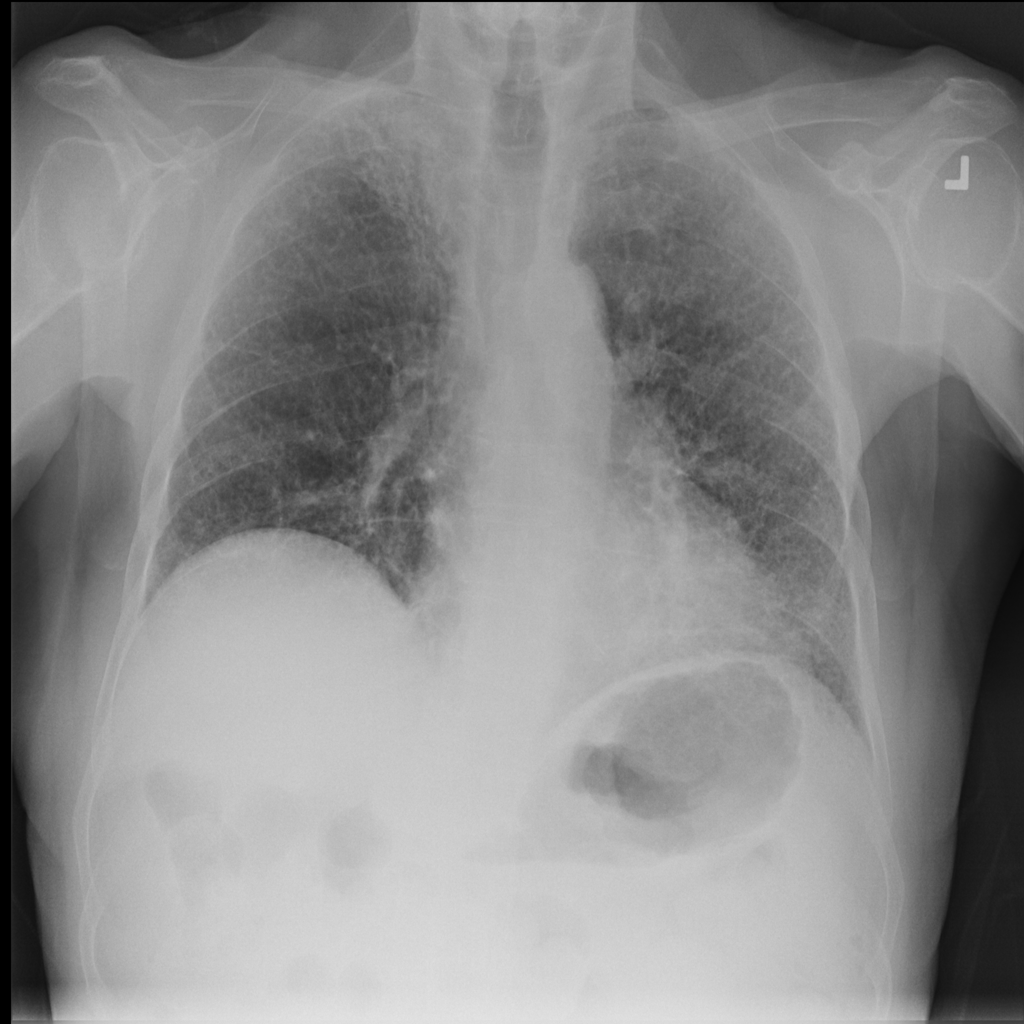

Consolidation

Consolidation refers to air-space filling that makes part of the lung appear denser on imaging.

Showing up to 90 reference images for Consolidation.

PAT-531A · IMG-006Consolidation

PAT-531A · IMG-006

PA